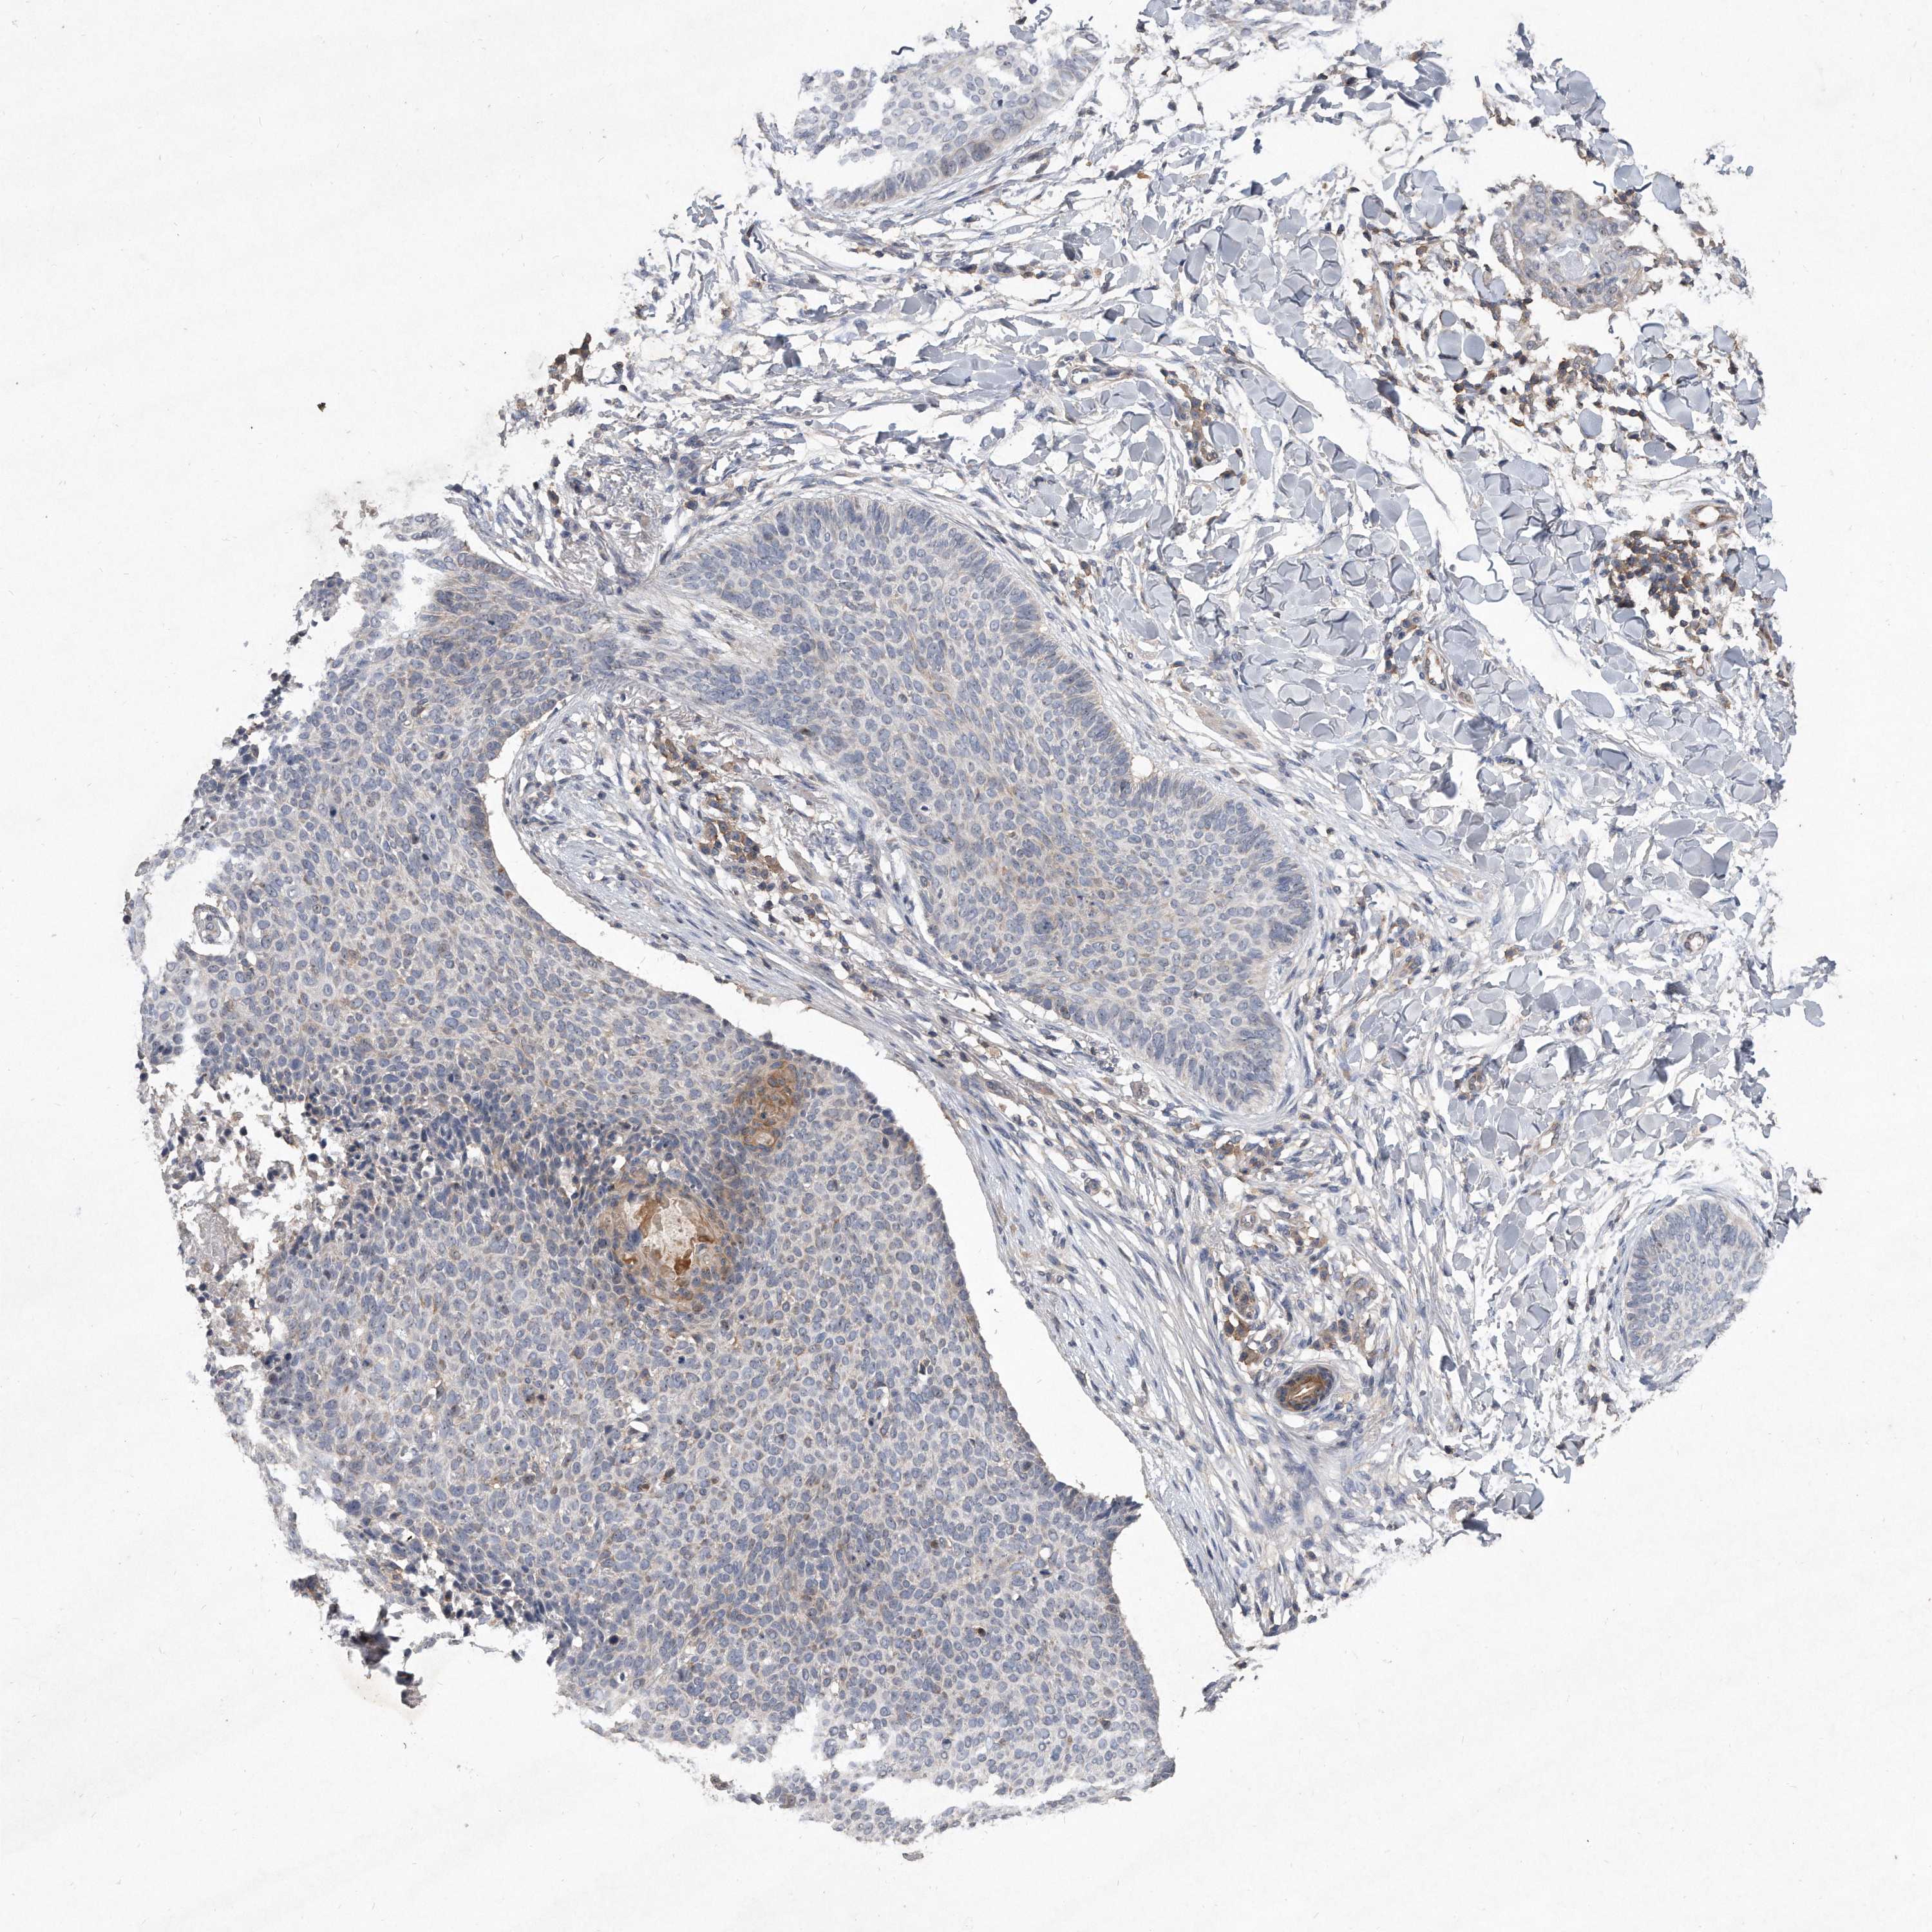

SKIN CANCER - Protein expressioni

A mouse-over function shows sample information and annotation data. Click on an image to view it in a full screen mode. Samples can be filtered based on level of antibody staining by selecting one or several of the following categories: high, medium, low and not detected. The assay and annotation is described here.

Each image is clickable and will lead to virtual microscopy that enables deeper exploration of all samples and also displays staining intensity scores, fraction scores and subcellular localization as well as patient and tissue information for each sample.

Antibody HPA029890

Squamous cell carcinoma, metastatic, NOS